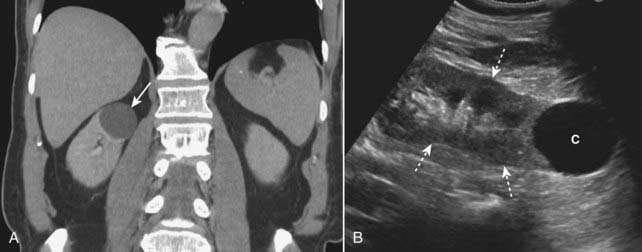

Cavernous Hemangiomas

imageCavernous hemangiomas are the most common primary liver tumor and second in frequency to metastases for localized liver masses. They are more common in women, are usually solitary and are almost always asymptomatic. They are complex structures composed of multiple, large vascular channels lined by a single layer of endothelial cells.

image Recognizing cavernous hemangiomas of the liver on CT and MRI:

Cavernous hemangiomas are usually hypodense lesions on unenhanced CT scans; they have a characteristic nodular enhancement from the periphery inward following injection of intravenous contrast and become isodense in the venous phase.

Contrast tends to be retained within the numerous vascular spaces of the lesion so that they characteristically appear denser than the rest of the liver on delayed (10 minute) scans (Fig. 18-33).

MRI is frequently the preferred modality in the evaluation of hemangiomas, as it is more sensitive than a nuclear medicine tagged red blood cell scan and more specific than a multiphase CT scan.

Similar to CT, hemangiomas on MRI usually have a characteristic nodular enhancement from the periphery inward following injection of intravenous contrast. Contrast tends to be retained within the numerous vascular spaces of hemangiomas so that they characteristically appear brighter than the rest of the liver on delayed (10 minute) scans (Fig. 18-34).

image

Figure 18-34 Cavernous hemangioma of the liver, MRI.

(A) This image (an axial T1-weighted image) demonstrates a well-circumscribed, slightly lobular dark mass in the right hepatic lobe (solid white arrow in all images). (B) Subsequent images following the administration of intravenous contrast (gadolinium) show peripheral-to-central enhancement, until the entire mass homogeneously enhances on a delayed 10-minute image (C). The combination of this enhancement pattern and the signal characteristics of the lesion allows an unequivocal diagnosis of hemangioma.